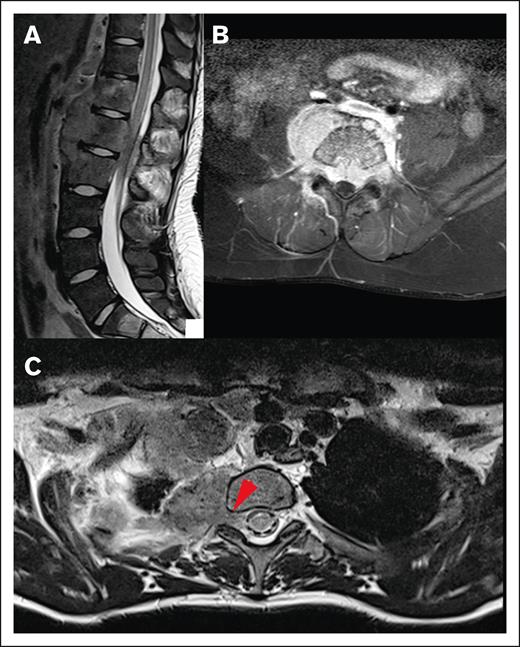

Different origins of CNS HL lesions. (A) Tumor originating from bone (vertebral body of T12, L1, and L2). (B) Unclear tumor origin but very likely bone, with circumferential involvement and an associated soft tissue component. (C) Paravertebral tumor mass of the upper thoracic spine infiltrating through the right neuroforamen, demonstrated by the red arrow, likely originating from soft tissue.